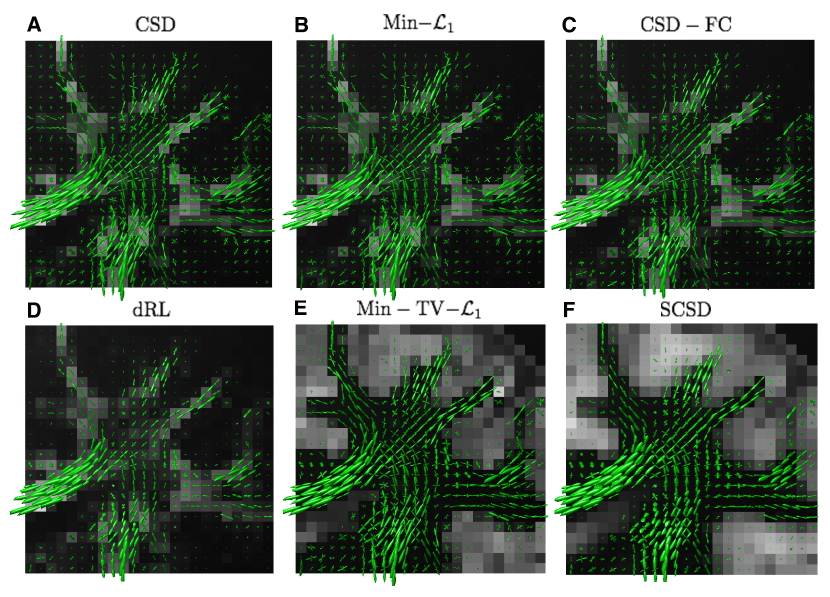

The reconstructions obtained for the same axial view and s/mm2 are depicted in Fig. 12, whose composition is identical to that of Fig. 10. Although fairly close in appearance to the previous case, these reconstructions allow us to make a number of important observations. First of all, as compared to the case of s/mm2, a wider bandwidth of the HARDI signals at s/mm2 leads to a better angular resolution, which is particularly noticeable in the case of dRL. Moreover, despite considerably worse noise conditions, the fODF reconstructions obtained by means of Min-TV- and SCSD have much less residual noise over the areas occupied by cortical grey matter, where isotropic diffusion is expected to prevail. This fact indicates the effectiveness of the regularization schemes exploited by these SD methods. Finally, a closer inspection of the glyphs in Fig. 12 reveals that the fODF reconstructions yielded by SCSD demonstrate a better spatial smoothness and anatomical consistency. The same observations can be made in the case of the coronal view, as shown in Figs. 13 and 14 for s/mm2 and s/mm2, respectively. (Note that the local region represented by these figures has been chosen according to the results in [44], which also provides indication of specific fibre bundles within the selected regions of interest).